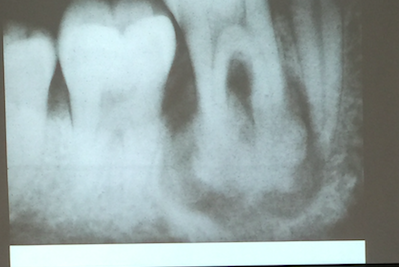

Cementoblastoma